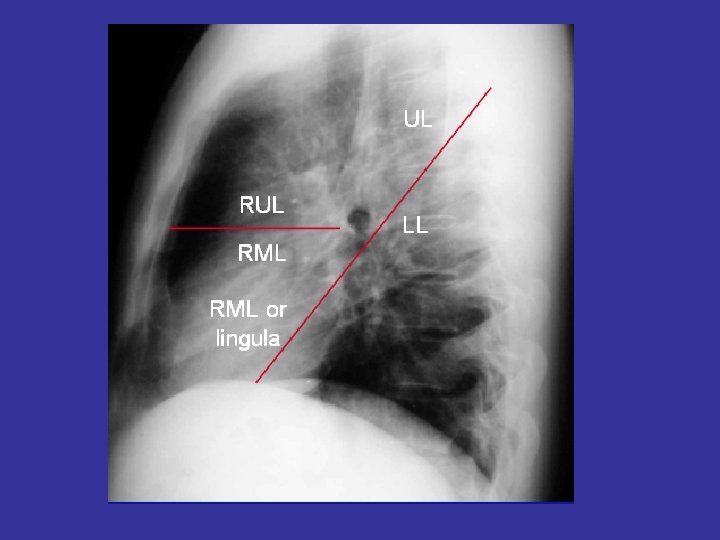

Lobes and Fissures

lateral view ? ! can detect otherwise hidden masses

The lateral chest film our best friend • Find abnormalities on the frontal film

The lateral chest film our best friend • Find abnormalities on the frontal film • Confirm abnormalities suspected from frontal film • Don’t be afraid to look at it